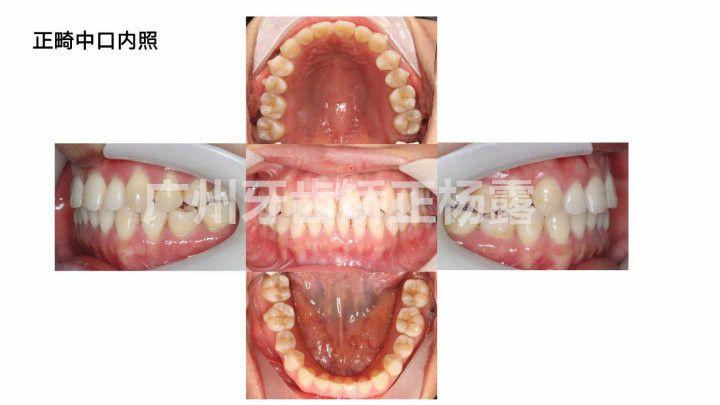

正畸前口内照

患者主诉:牙齿不齐

口内检查:

上颌中线正中,下颌中线右偏1mm,前牙部分反合,笑线不调。磨牙关系右侧I类,左侧I类,上颌牙弓I度拥挤,上颌牙弓中段狭窄。18、38垂直阻生,28未萌出。面部检查:

五官基本对称,面部左右基本对称。口裂大小与双侧瞳孔内缘切线宽度一致。面下1/3过短,直面型。诊断:

牙型:AngleI类骨型:I类拥挤:I度前牙部分反合牙弓不调、笑线不调患者存在的问题:

上颌牙弓拥挤,牙列不齐;前牙部分反合;笑线不调。方案设计: